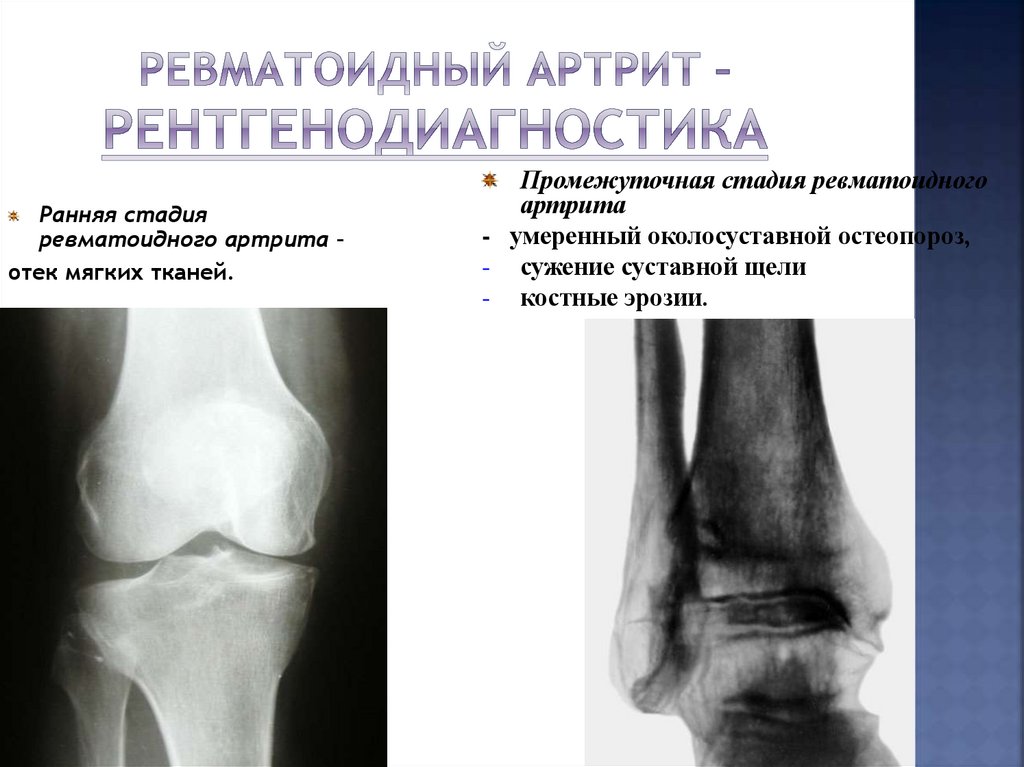

Ревматоидный артрит – рентгенодиагностика